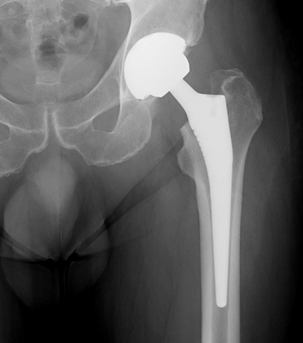

xray of a successful Total Hip ReplacementTotal Hip Replacement is an effective procedure that reduces pain, increases function and increases quality of life.

There are many different types of hip replacement in common use today such as cemented or uncemented types with a variety of bearing surfaces such as metal, polyethylene and ceramics. Each particular type has its own advantages and disadvantages and these can be discussed in detail with Mr Emms during your consultation. The choice of implant is made on several factors which can be discussed during your consultation.